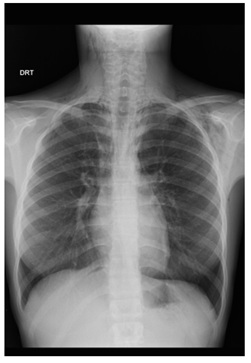

She underwent CT-Scan, which revealed widespread emphysema, that dissected the laterocervical mucle-aponeurosis plans from the skull base to the supraclavicular fossa, on the right, and the shoulders, on the left (Figure 2). The exam showed the presence of pneumomediastinum and bilateral pneumothorax (Figure 3).

Figure 2: Cervical and thoracic CT-Scan (coronal, non-contrast) demonstrating extensive emphysema extending through the neck, from the cranial base to the supraclavicular fossa, on the right and the shoulders, on the left.